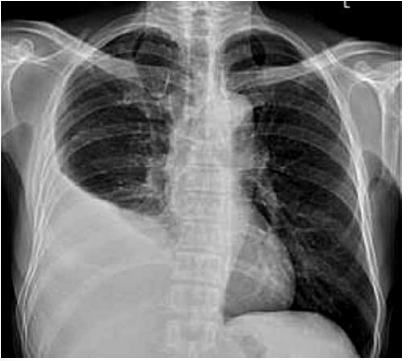

Paciente de 28 anos, procedente de zona de garimpo,

tabagista e etilista, apresenta queixa de tosse seca e dor

torácica à direita há trinta dias, com febre esporádica.

Apresenta episódios de tosse com secreção amarelada

e laivos de sangue há dez dias, sem melhora ou piora.

Emagreceu 6 kg no período de quarenta dias. Exame

físico: emagrecido, Tax: 37,4 ºC, submacicez e murmúrio

vesicular diminuído em base do hemitórax direito.

Radiografia de tórax a seguir:

(Arquivo pessoal; imagem usada com autorização)

O diagnóstico e a conduta corretos são, respectivamente: